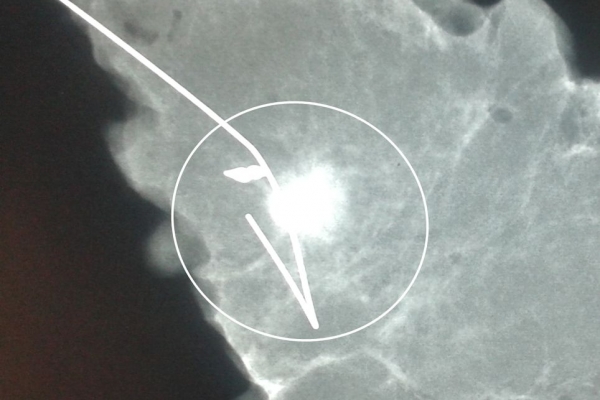

Σε περίπτωση που απαιτείται η χειρουργική αφαίρεση ενός ευρήματος που δε ψηλαφάται από το χειρουργό, τότε γίνεται η τοποθέτηση αγκίστρου σήμανσης (hook) λίγο πριν το χειρουργείο. Το άγκιστρο έχει σκοπό να καθοδηγήσει το χειρουργό για την αφαίρεση του σωστού τμήματος του μαστού, ώστε να αφαιρεθεί με ασφάλεια η ύποπτη βλάβη χωρίς να επηρεασθεί η αισθητική εικόνα του μαστού, πράγμα πολύ σπουδαίο ειδικά σε νέες γυναίκες και σε γυναίκες με μικρό μαστό.